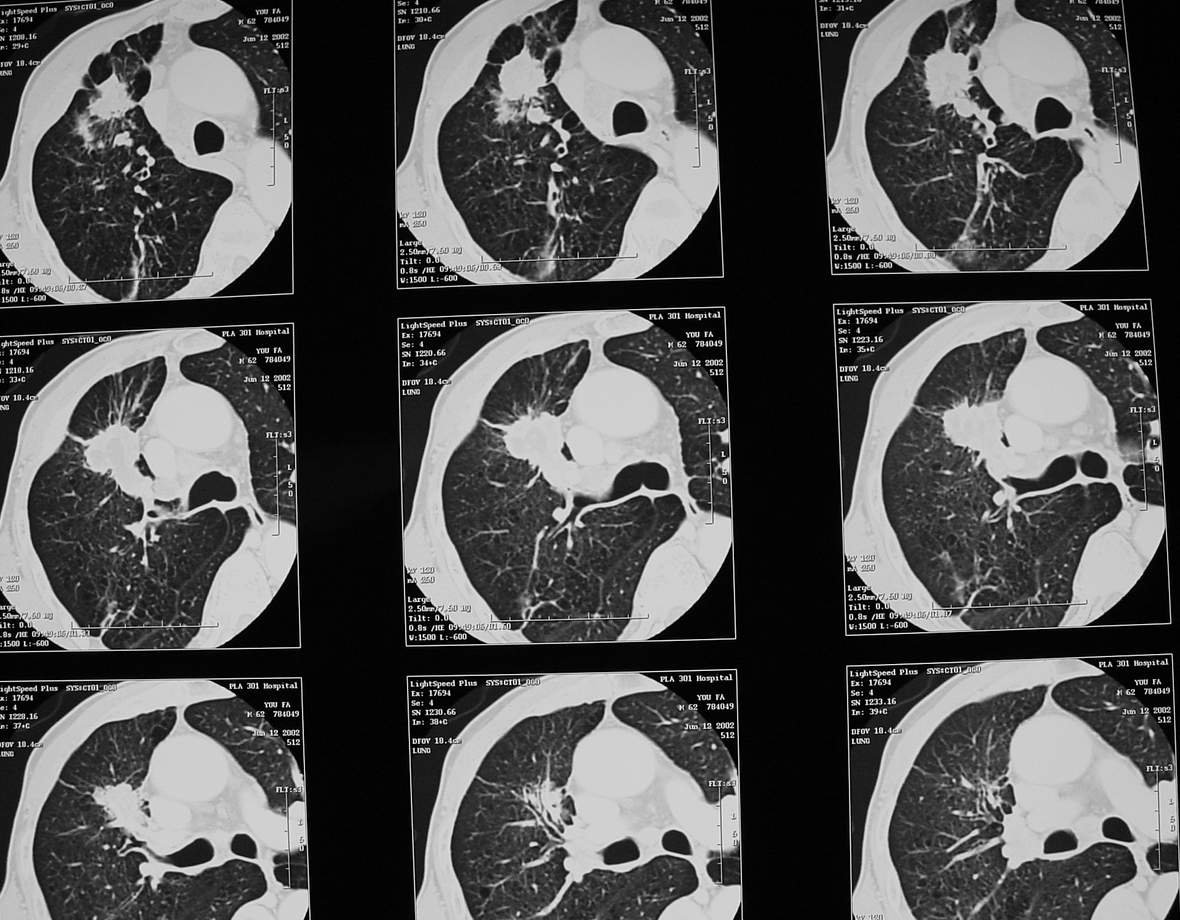

男,64岁,咳嗽、咳痰20余天,明显消瘦,x线片发现肺部阴影

长毛刺、肺门引流征象、中心液化坏死等应该是提示结核性肿块的可能性大,但是合并椎体及多处肋骨破坏则周围型肺ca并椎体及多处肋骨转移不能除外。

1)右肺上叶前段周围型肺癌并阻塞性肺炎、右肺门及纵隔淋巴结转移、肋骨及胸椎转移。2)右肺上叶后段纤维病灶。

xiang 肺癌肋骨转移;需出外韦氏肉芽肿

考虑矽肺合并肺癌并转移